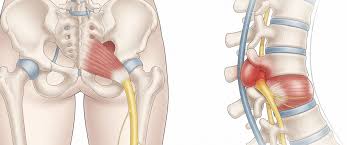

इस बीमारी को समझने के लिए पुडेंडल नर्व को समझना जरूरी है। पुडेंडल नर्व श्रोणि (Pelvis) के निचले हिस्से में स्थित मुख्य नसों में से एक है।

- उत्पत्ति: यह रीढ़ की हड्डी के सबसे निचले हिस्से (S2, S3, और S4 नसों के समूह) से निकलती है।

- मार्ग: यह पेल्विक क्षेत्र की मांसपेशियों और स्नायुबंधन (Ligaments) के बीच से होकर गुजरती है, विशेष रूप से एक संकीर्ण मार्ग से जिसे ‘एल्कॉक कैनाल’ (Alcock’s canal) कहा जाता है।

- कार्य: यह तंत्रिका हमारे जननांगों (पुरुषों में लिंग और अंडकोश, महिलाओं में क्लिटोरिस और योनि के बाहरी हिस्से), पेरिनेम (गुदा और जननांगों के बीच का हिस्सा) और गुदा (Anus) को संवेदना (Sensation) प्रदान करती है। यह मल और मूत्र को नियंत्रित करने वाली मांसपेशियों (Sphincters) को भी नियंत्रित करने में मदद करती है।

जब यह नस अपने संकरे रास्ते में कहीं भी दब जाती है, तो पुडेंडल न्यूराल्जिया की समस्या पैदा होती है।